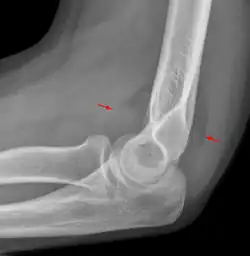

Fettpolsterzeichen

Das Fettpolsterzeichen ist ein Röntgenzeichen, welches zur Erkennung einer Fraktur bzw. einer okkulten Fraktur hilfreich sein kann.

Es handelt sich um die Darstellung von normalen anatomischen Fettpolstern an Gelenken als Aufhellungsband. Je nach Skelettregion sind diese Fettpolster beim Gesunden sichtbar oder nicht. Eine Verlagerung oder das Sichtbarwerden durch einen Gelenkerguss weist auf eine Fraktur hin.

Das bekannteste Fettpolsterzeichen ist das am Ellenbogen.